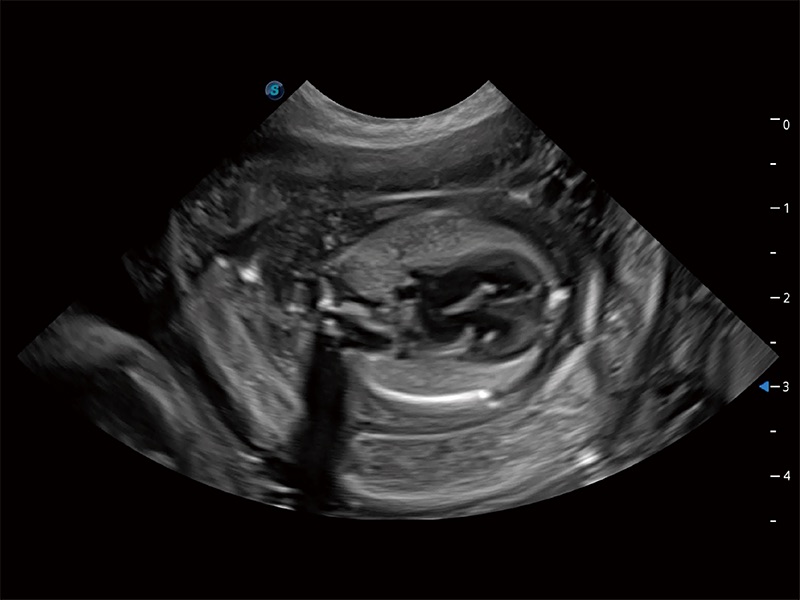

动物是人类最亲密的朋友和最值得信赖的伙伴。米兰官方网站也一直致力于探索动物专用的超声影像解决方案。全新推出的ProPet系列,是米兰官方网站在动物超声影像智能化、专业化、精准化的一次跨越式革新。动物不能用言语来表述自己的不适,通过超声影像,ProPet系列搭建了动物医生与不同物种沟通的“桥梁”,为动物医生注入了“治愈之力”。 ProPet 80 是米兰官方网站匠心打造的一款高端动物专用彩超,采用性能卓越的全新硬件架构,极大提升超声系统的运行效率和数据处理能力,帮助动物医生从容应对日益增多的挑战性病例和日益多样化的临床需求。

高性能和先进的临床应用工具可以为动物医生提供临床信心。ProPet 80 搭载了先进的腹部和浅表应用工具,帮助医生在日常临床实践中发挥前所未有的作用。

ProPet 80 专为动物医生设计,对不同的动物体型和生理结构作出了针对性的优化。通过动物影像专用软件,可满足个性化的应用需求,帮助动物医生获得更精确的诊断数据。